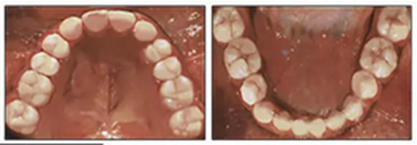

兩年半后,在上下牙弓上均實現(xiàn)了間隙關(guān)閉,并且使用0.017×0.025英寸的不銹鋼弓絲進行咬合精細調(diào)整(圖8)。去除托槽后,上下頜采用舌側(cè)弓進行保持(圖9)。

由于美觀和功能原因,要求恢復(fù)上頜尖牙和前磨牙,但患者希望推遲至成年后繼續(xù)這些治療。

五、治療結(jié)果

總體治療目標已經(jīng)實現(xiàn)。病人的笑容和輪廓有所改善。咬合關(guān)系為I類磨牙關(guān)系,牙列整齊,牙尖交錯關(guān)系良好。反合和中線偏移得以矯正,并實現(xiàn)了正常的覆蓋和覆合。上下牙弓的擁擠問題完全解決,并且完成后全景片顯示良好的牙根傾斜度。疊加顯示良好的縱向和垂直控制(ANB,3.5°; SN / GoMe,42.5°)和矯正上下頜前牙傾斜度(1 / SN,96°; IMPA,87°)(圖10 ; 表)。

在治療結(jié)束時沒有觀察到顳下頜關(guān)節(jié)紊亂的體征或癥狀,但發(fā)現(xiàn)了輕微的牙根吸收以及裂隙區(qū)域的骨頭輕度丟失。

治療持續(xù)3年,患者始終保持積極和合作。口腔衛(wèi)生很好。患者和她的父母都對結(jié)果感到滿意。經(jīng)過24個月的保持后,咬合保持得很好(圖11 ; 圖12)。在上牙弓中,應(yīng)用固定舌側(cè)保持器以防止任何復(fù)發(fā)傾向。在下牙弓中,治療后拔除第三磨牙。